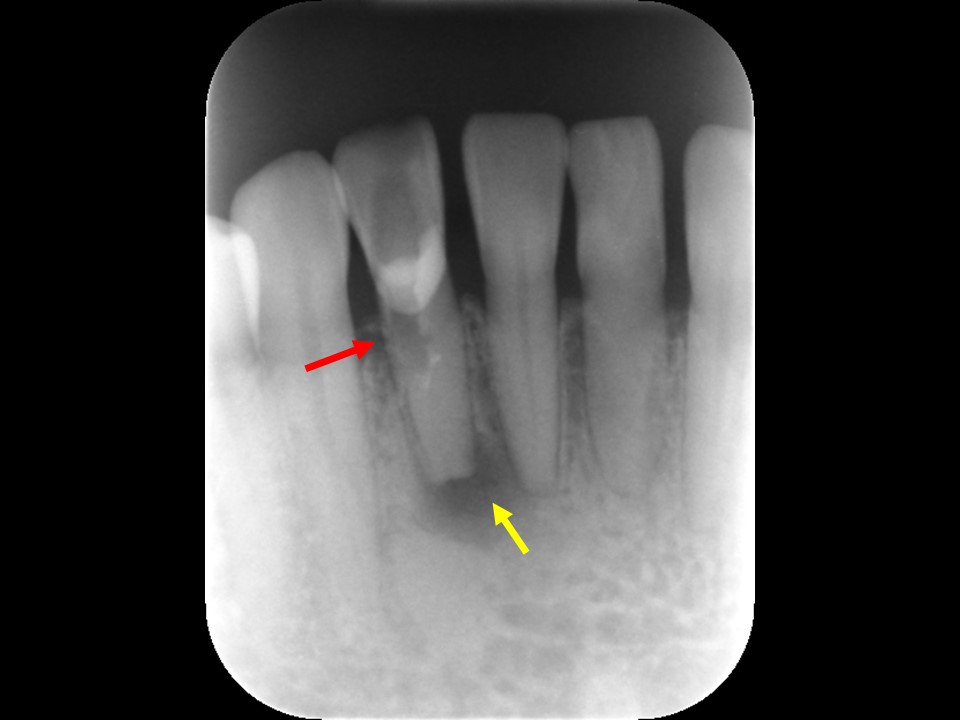

根管充填3か月後のCT画像にて、根尖病変および歯性上顎洞炎の予後を確認しました。根尖病変は顕著に縮小して骨の再生が見られ、上顎洞炎はほぼ治癒していました(下写真)。

根管治療14か月後のレントゲン及びCT画像では、根尖部のX線透過像および上顎洞内の不透過像は完全に消失しているのが分かります(下写真)。根尖部の骨の再生と上顎洞の正常化が認められ、根尖病変ならびに歯性上顎洞炎は完全に治癒しました。

根管充填3か月後のCT画像です。根尖病巣は顕著に縮小しており、骨の再生を認めます(赤矢印)。上顎洞の炎症も消退し、ほぼ正常像を呈していることが分かります(黄矢印)。病状が治癒傾向を認めるため、歯冠修復処置を行っていきます。

根管治療14か月後のレントゲンおよびCT画像です。術前にあった根尖部のX線透過像(赤矢印)ならびに上顎洞内のX線不透過性の亢進(黄矢印)は完全に消失し、根尖病変および歯性上顎洞炎は良好に治癒しているのが確認できます。